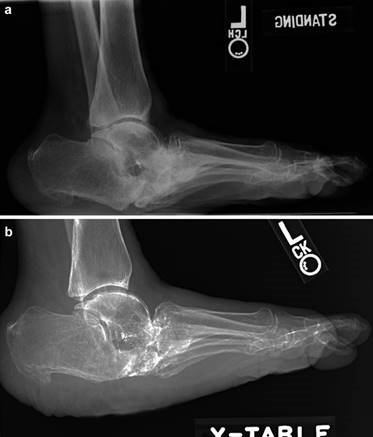

Weight-bearing anteroposterior (AP), lateral, and sesamoid axial radiographs are mandatory. On the AP view, the surgeon measures the Hallux Valgus Angle (HVA, normal < 15°), the Intermetatarsal Angle (IMA, normal < 9°), and the Distal Metatarsal Articular Angle (DMAA). The lateral view is scrutinized for Meary's angle (talo-first metatarsal angle) to identify midfoot collapse, as well as the presence of dorsal osteophytes indicative of hallux rigidus. The sesamoid axial view is critical for assessing the degree of sesamoid subluxation and the integrity of the crista.

Clinical & Radiographic Imaging Archive